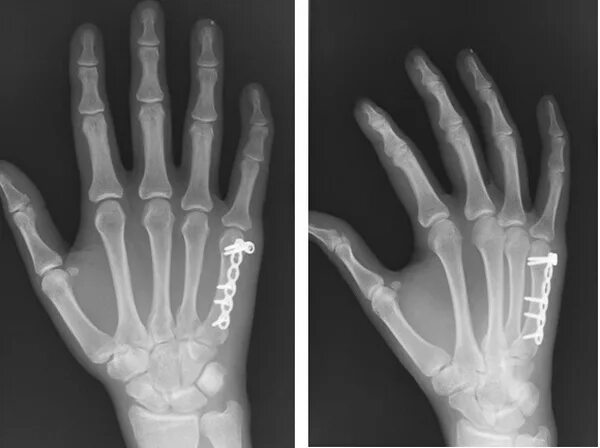

Остеосинтез 2 пястной кости. остеосинтез 5 пястной кости. остеосинтез 5 пястной кости кисти спицей. остеосинтез пястной кости спицами.

Остеосинтез фаланги пальца. остеосинтез пястной кости спицами. остеосинтез фаланг пальцев кисти. остеосинтез пястных костей винтами рентген.

Перелом 5 пястной кости кисти. остеосинтез 2 пястной кости. остеосинтез 5 пястной кости. спица киршнера перелом 5 пястной кости.

Остеосинтез 2 пястной кости. перелом 1 пястной кости остеосинтез. перелом второй пястной кости остеосинтез. остеосинтез пятой пястной кости кисти.

Остеосинтез 2 пястной кости. остеосинтез фаланги пальца. остеосинтез фаланги пальца кисти.

Остеосинтез 2 пястной кости. остеосинтез проксимальной фаланги. остеосинтез фаланги пальца кисти. остеосинтез фаланг пальцев кисти.

Остеосинтез пятой пястной кости. оскольчатый перелом пястной кости. остеосинтез пятой пястной кости кисти. мкб перелом пястных костей кисти.